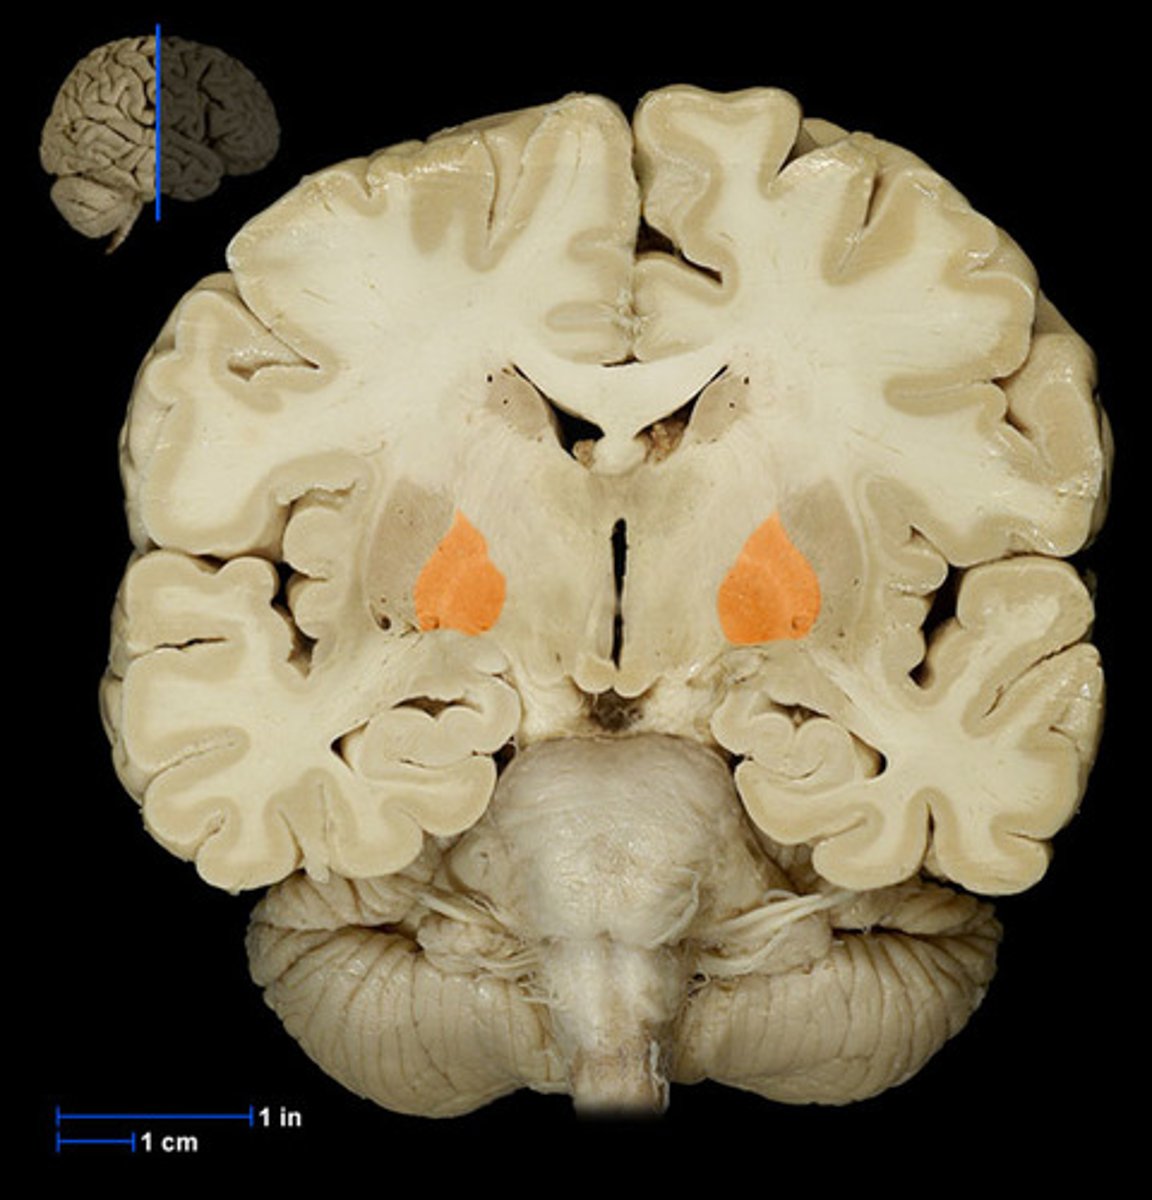

Subthalamic nucleus location and role

Inferior to thalamus

Splidle or lens shaped

Communicates with globus pallidus

Substantia nigra segments and their loaction and role

Pars compacta → contains darkly pigented dopaminergic neurons (more dorsal)

Pars reticulata → involved in output for eye movements, inhibits thalamus (more ventral)